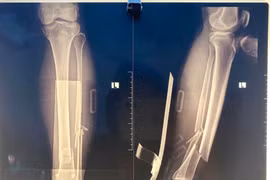

Không thể cử động chân, người đàn ông 71 tuổi gãy kín 2 xương

Gãy xương kín là hiện tượng xương gãy nhưng không đâm xuyên qua da nên thường được thực hiện điều trị muộn sau vài ngày hoặc vài tuần chấn thương.